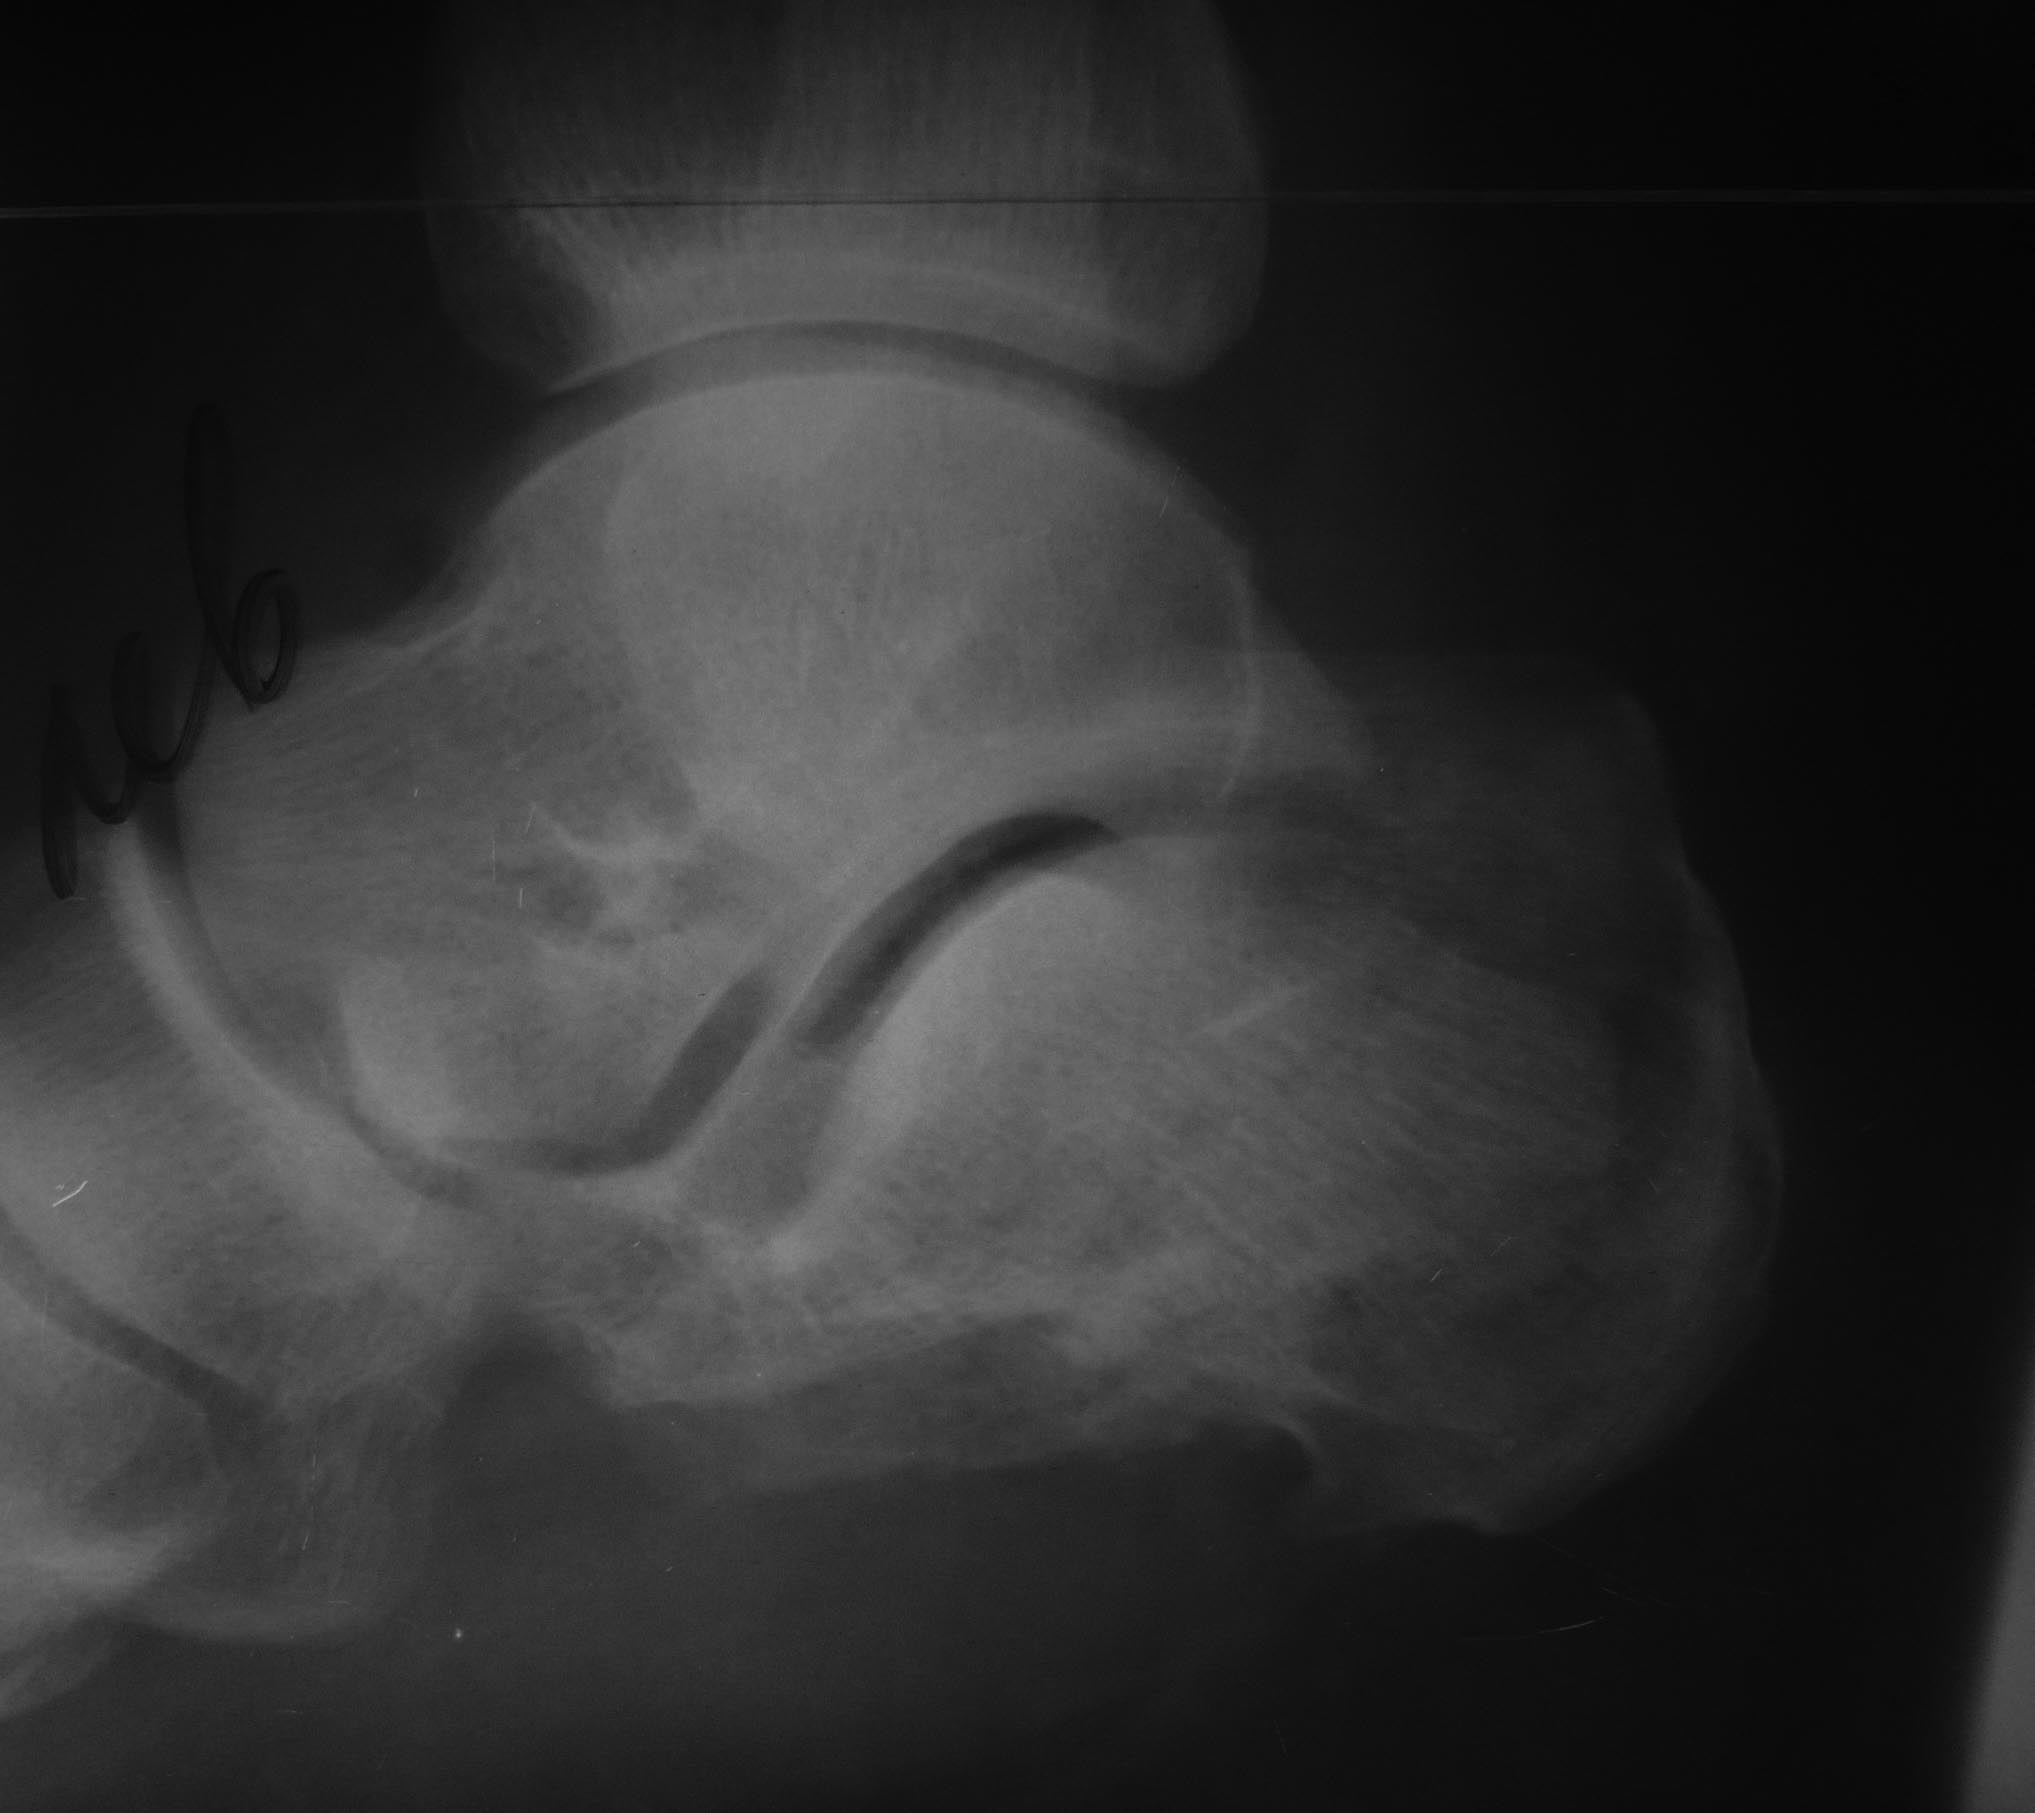

Пациент 53 года поступил 23.04.17 после падения со второго этажа. Ds:

Сочетанная травма ЗЧМТ. СГМ. О. перелом 3А (по Gustilo-Andersen) левой

пяточной кости.Рана около 10 см по внутренней поверхности г/стопного

сустава с переходом на пяточную область. Края раны не осаднены,

жизнеспособны.

Выполнена ПХО, устранение грубого смещения, фиксация спицами,

гипсовая иммобилизация. На 26.04.17 рана без воспаления, отделяемое

минимально геморрагическое.